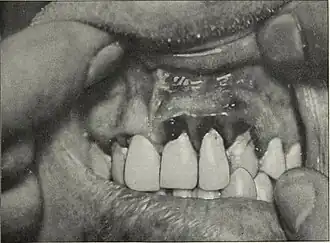

Inflammation des tissus mous sur les maxillaires avant le geste chirurgical connu avec le bistouri, photo de revue médicale 1912.

La gingivoplastie désigne le traitement chirurgical de l’os (mandibule, maxillaire) ou de la gencive lorsqu'ils sont abimés, nécrosés ou déformés[1].

Le premier geste le plus courant est celui de la mise à nu de l'os par la découpe de l'excès de tissu de gencive sur les maxillaires ; en France, ce geste est appris en école dentaire.